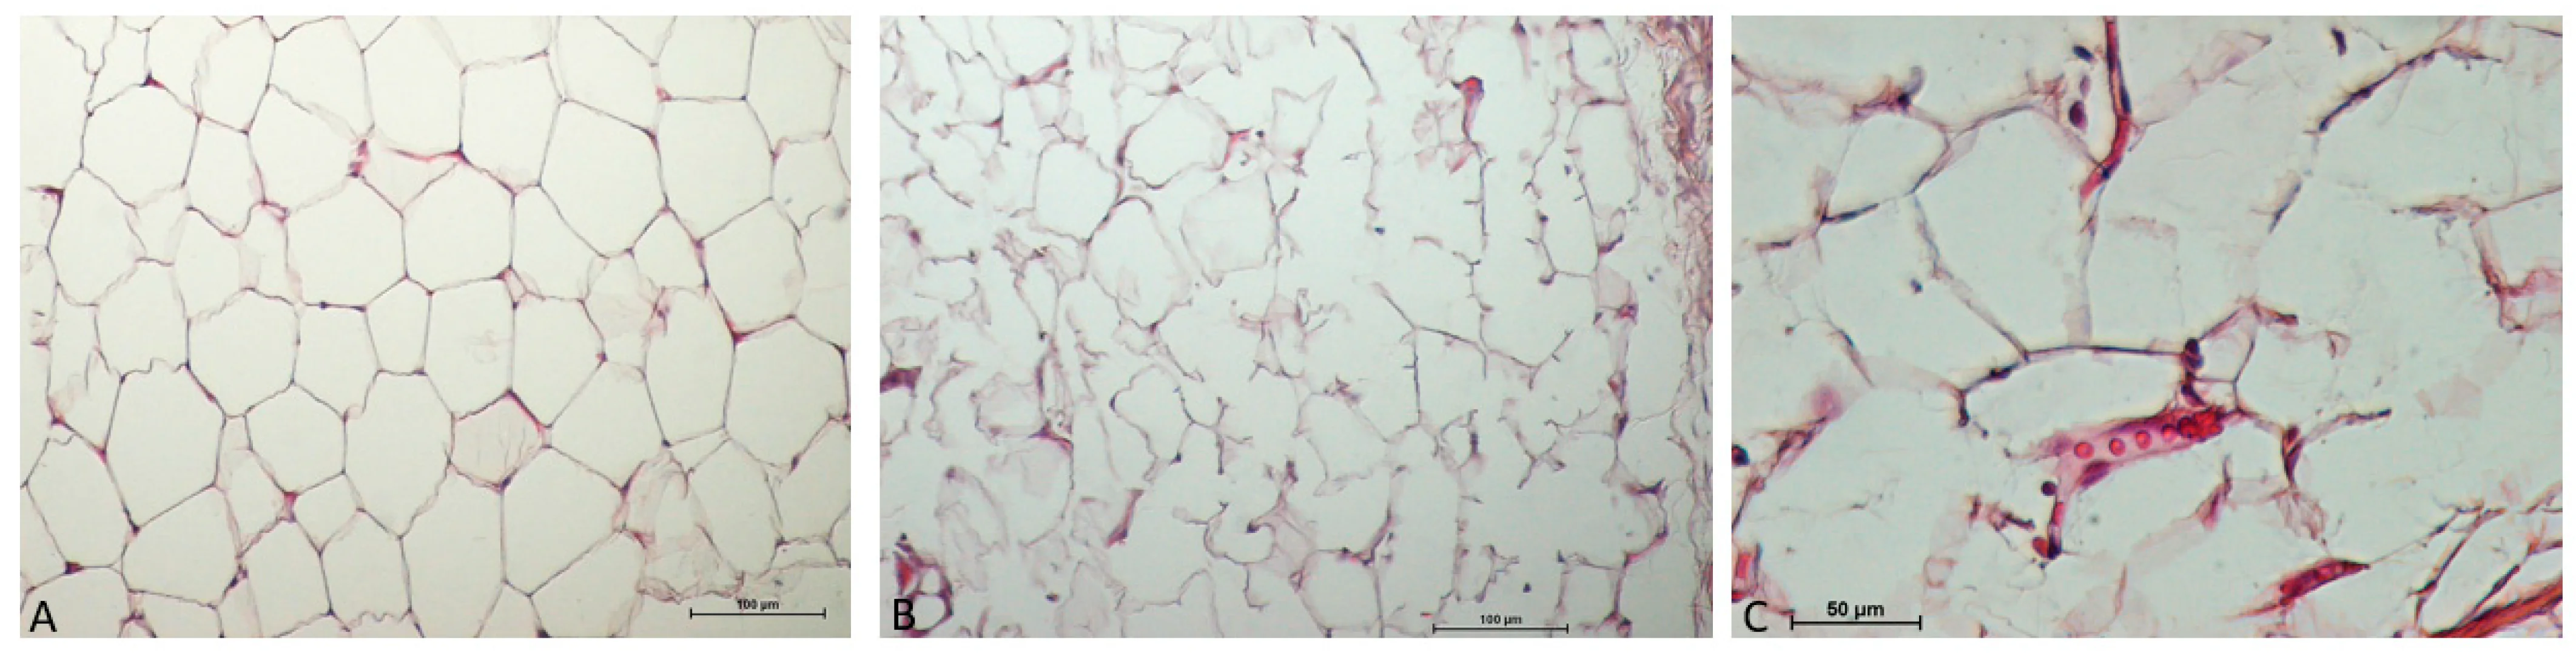

극초단파 (microwave)를 통한 효과적인 지방 분해

온다리프팅은 피부 표면을 손상시키지 않고 피하지방층에만 선택적으로 열 에너지를 전달하도록 설계되었습니다.

그 결과 지방세포막이 손상되고 세포 사멸이 일어납니다.